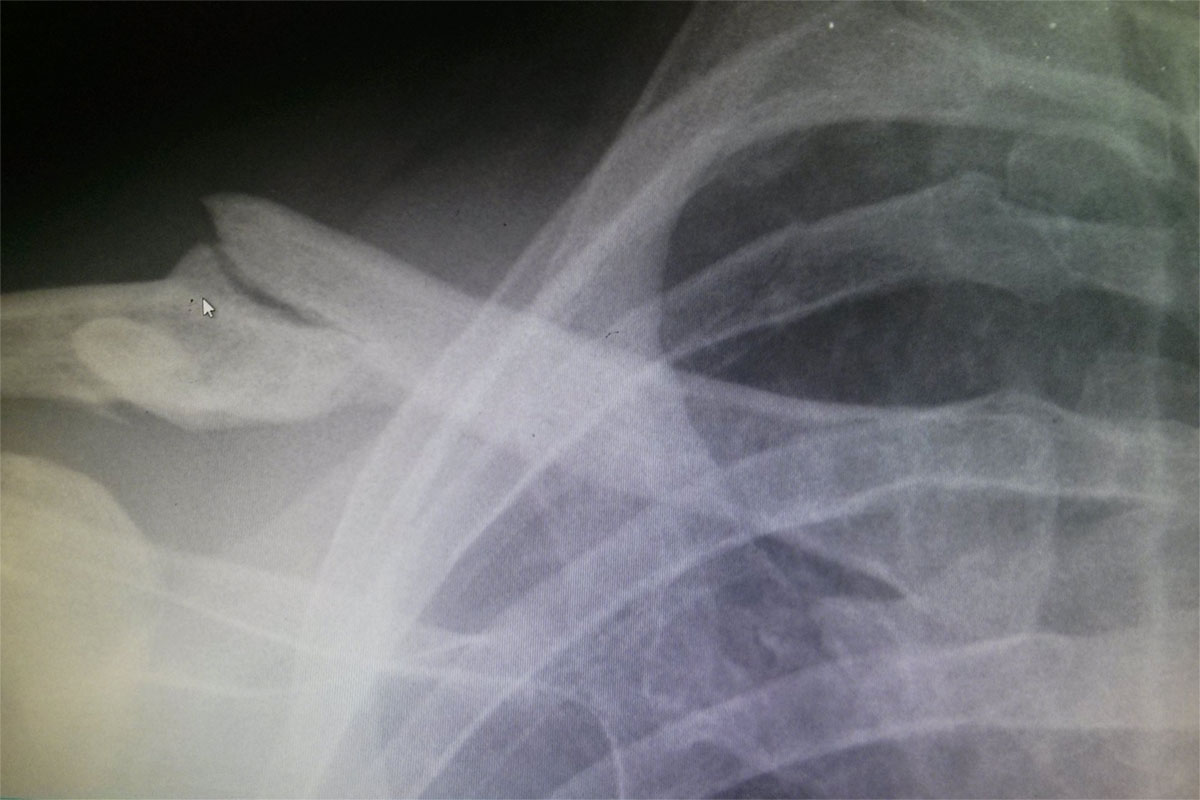

Matt's second broken collarbone

Lightning does strike twice – another broken collarbone

Lightning can strike twice, with another broken collarbone for Matt